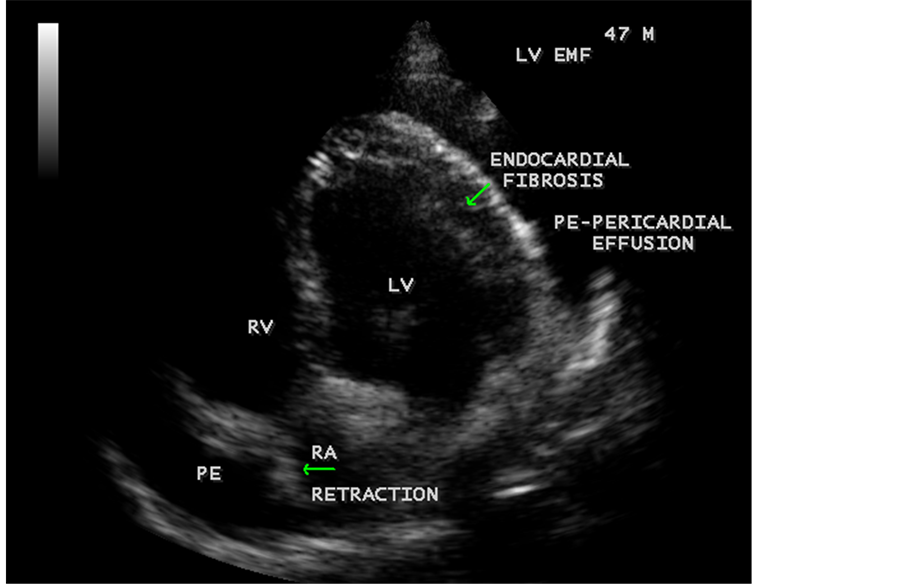

Figure 42. Showing Endomyocardial fibrosis with moderate pericardial effusion and right atrial notch (RA retraction) in a 47-year-old male.

Figure 43. Endomyocardial fibrosis showing subtricuspid fibrosis, aneurysmal right ventricle, mild pericardial effusion and right atrial notch (RA retraction) in a 14-year-old male.

Today echocardiography is used as the screening tool at the community level as the diagnosis of EMF could be confirmed at the bedside. Echocardiography accurately assesses the pathological abnormalities of chronic disease and it is the gold standard technique for the diagnosis of EMF [36] . It reveals dense endomyocardial echocardiograms along different parts of the mural and valvular endocardium and AV valve dysfunction [37] as shown in Figure 3 to Figure 7, Figure 10 to Figure 15, Figure 17, Figure 18, Figure 20 to Figure 75 and Figure 78 to Figure 84. The typical feature of EMF is the obliteration of trabecular portion of the ventricle and in advanced cases, there is shrinkage of the cavities creating an apical notch, regurgitation, slow flow with spontaneous echo contrast as in Figure 36 and considerable pericardial effusion. Similar to apical notch of right ventricle, a right atrial notch is well seen as contraction (or retraction) of tricuspid annulus as in Figure 41 and right atrial notch as in Figure 42 and Figure 43, indicating the retraction of right atrial cavity as a peculiar feature of right ventricular EMF. Biventricular enlargement as shown in Figure 41 and biatrial

enlargement as in Figure 33 are the characteristic features of advanced stage of EMF. The fibrosed muscular trabeculae extending into the cavities from the walls of the chambers in the right ventricle visible as “cobra heads” as in Figure 4 and in pericardial sac as in Figure 29. Aneurysmal right ventricle with scattered areas of fibrosis in the sub tricuspid region and a notch in the right atrium is well seen in a 14-year-old boy as in Figure 43. Right atrial notch is frequently noticed in EMF patients as shown in Figure 42 in a 47-year-old male with left ventricular EMF and moderate pericardial effusion.